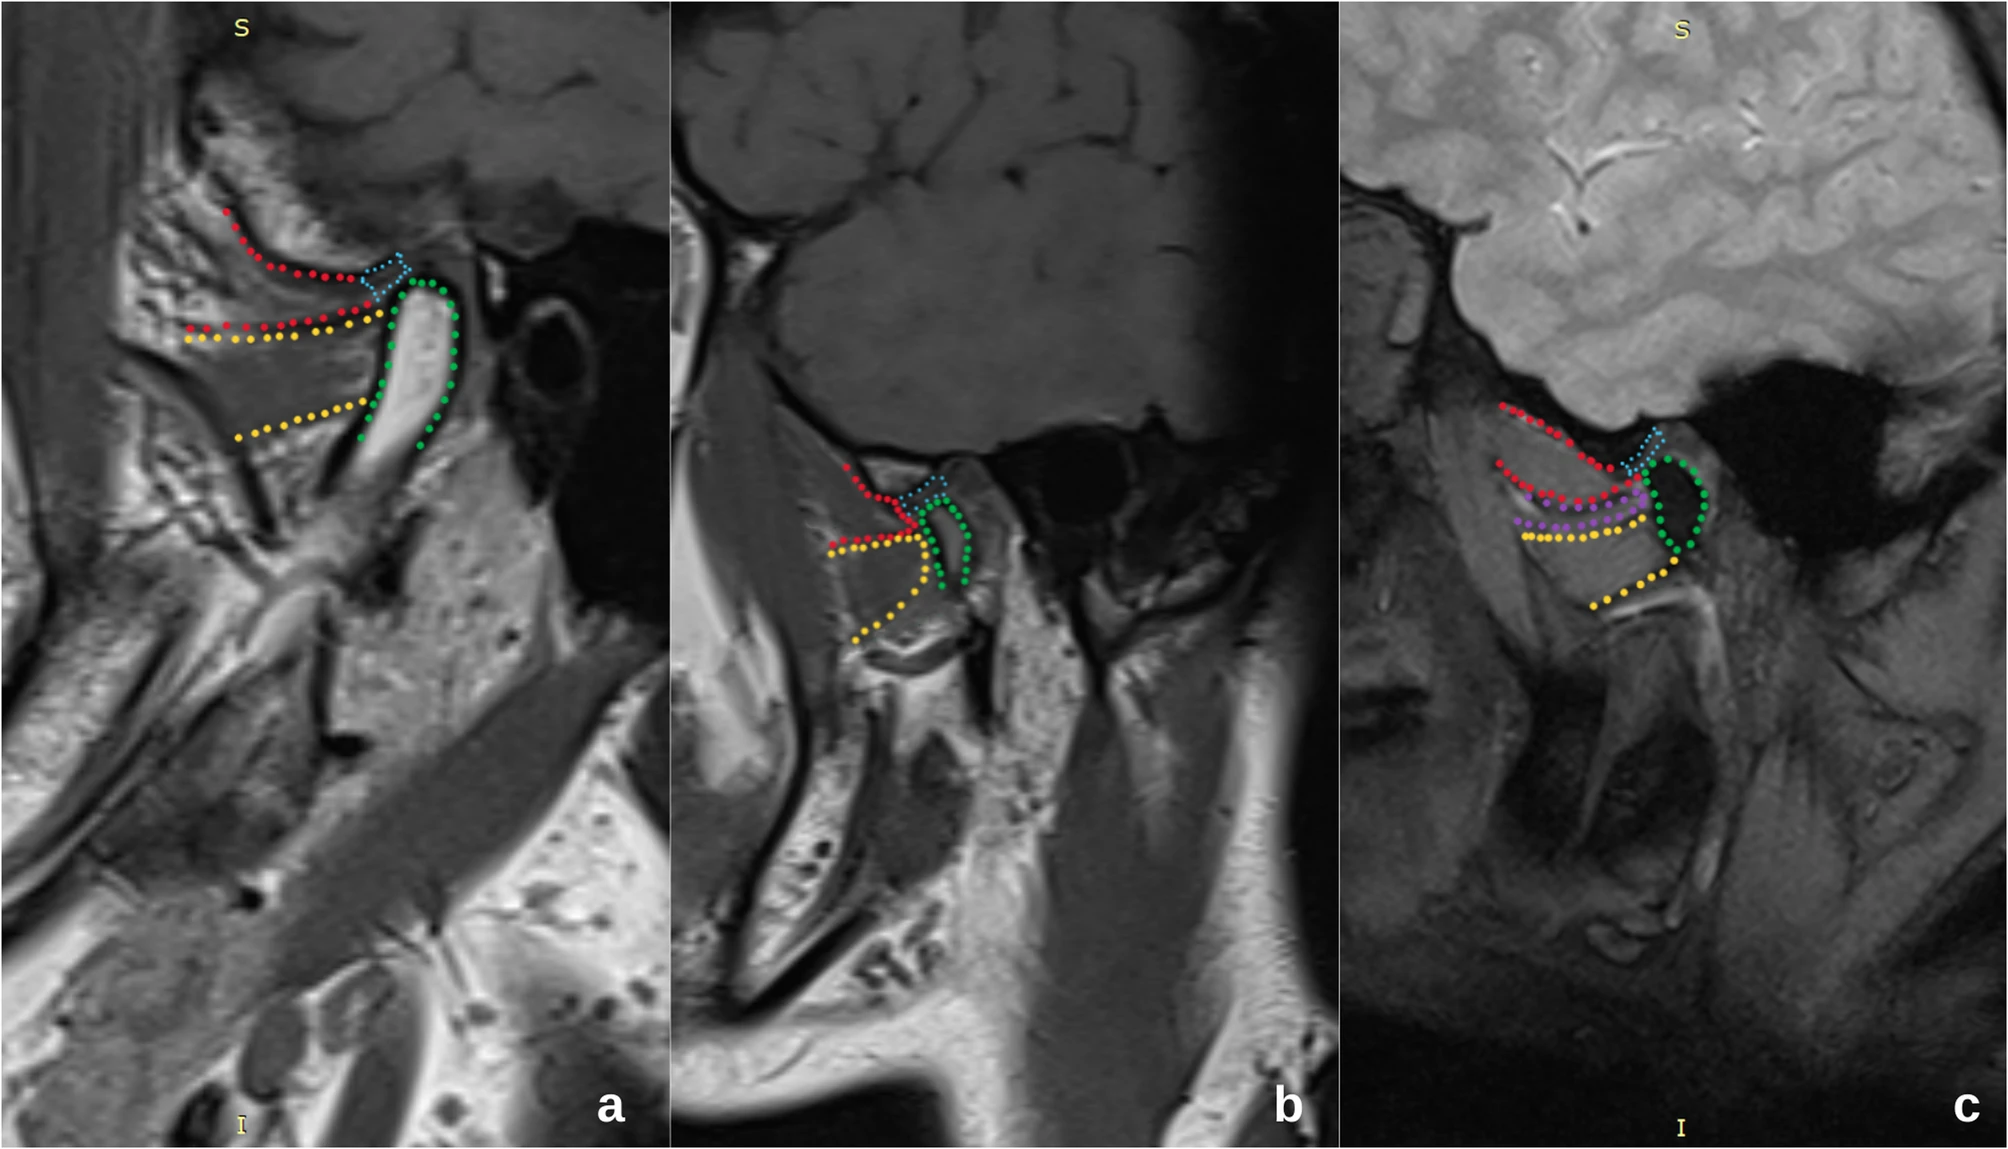

MRI provides superior soft tissue contrast, making it the gold standard for TMJ assessment. It allows for detailed visualization of the articular disc, condyle, joint capsule, and surrounding musculature without exposure to ionizing radiation. MRI sequences such as proton density and T2-weighted images are particularly effective in identifying disc position, joint effusion, and inflammatory changes.

Assessment of Articular Disc Displacement

Using MRI, clinicians can categorize the precisely displaced position of the articular disc, determine whether it is reducible, and assess any associated morphological changes. The imaging typically involves both closed-mouth and open-mouth positions to evaluate dynamic movement of the disc during jaw motion.

MRI Findings on the Lateral Pterygoid Muscle

MRI assessment extends beyond the disc itself to include the lateral pterygoid muscle. Changes such as muscle hypertrophy, atrophy, or abnormal signal intensity can indicate muscle overuse, fatigue, or inflammation, which may correlate with disc displacement patterns. Specifically, an **increased thickness or irregularities** may suggest compensatory mechanisms or muscular dysfunction contributing to joint instability.

A notable study published in BMC Oral Health explored the relationship between articular disc displacement and the morphology and function of the lateral pterygoid muscle using MRI. The findings indicated that patients with disc displacement, particularly those without reduction, often exhibited significant alterations in the lateral pterygoid muscle, such as hypertrophy or abnormal signal intensity, compared to asymptomatic controls.